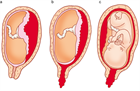

1. 常位早期剥離の初期症状は、切迫早産と極めて類似しているので注意を要する(推奨度2)

1. 性器出血、下腹痛、子宮収縮に異常胎児心拍パターンを認めた場合は常位胎盤早期剝離を疑う(推奨度2)